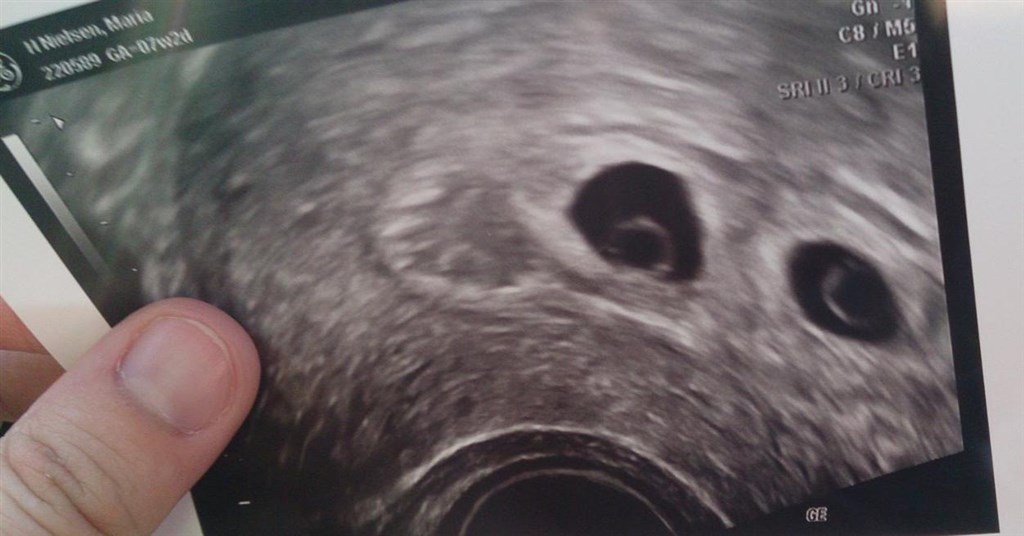

Billede fra tidlig scanning uge 7

Her er mit billede fra dagen scanning.

Umiddelbart ser det ud til at det er tvillinger og at du ikke er så langt henne.

Jeg sys det ligner tvillinger

Er det bare mig eller er det som om der er endnu en sæk helt til venstre?

Du venter da tvillinger